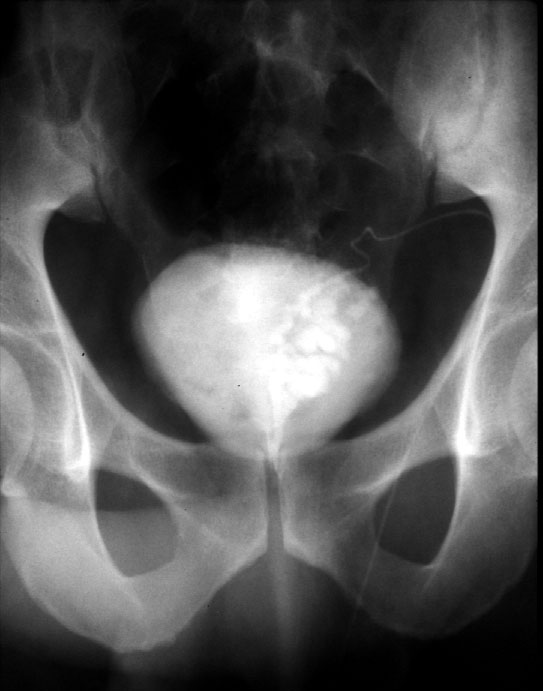

Note. The left seminal vesicle has been injected with contrast material.

Identify -- urinary bladder, vas, seminal vesicle